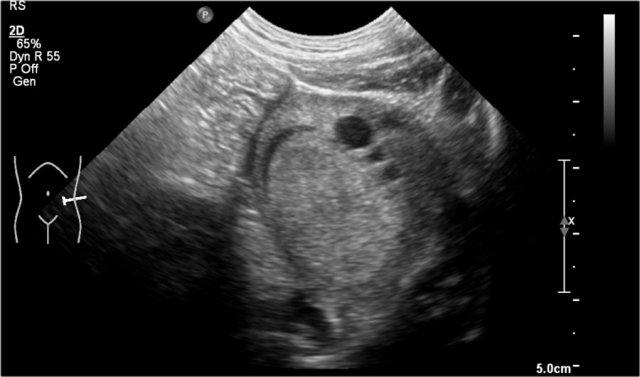

Bé trai một tuổi nhập viện vì bụng phình to.

Siêu âm phát hiện một tổn thương dạng nang kích thước lớn, trải dài từ gan xuống vùng chậu.

Ghi nhận có một số cặn lắng bên trong.

Ảnh MRI mặt phẳng coronal chuỗi xung T2W cho thấy rõ hơn mức độ lan rộng của tổn thương.

Trong phẫu thuật, tổn thương được xác định bám vào đại tràng lên, đại tràng này đã được cắt bỏ cùng với u nang bạch huyết.